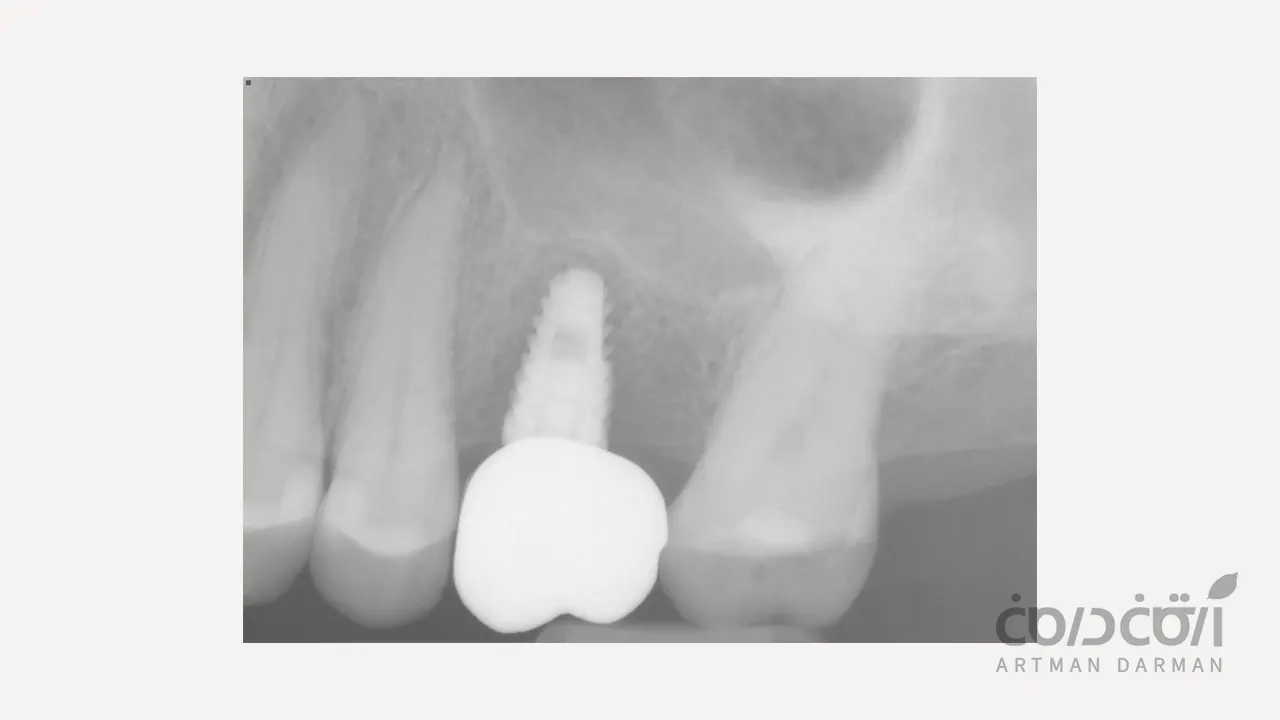

مرحله اول: خارج کردن ایمپلنت شکست خورده (Explantation)

این مرحله بسیار حساس است و هدف اصلی آن، خارج کردن ایمپلنت با حداقل آسیب ممکن به استخوان باقیمانده است. اینجا ممکن است با دو حالت احتمالی روبرو شویم:

اگر ایمپلنت لق باشد

در موارد شکست زودهنگام که ایمپلنت هنوز به استخوان جوش نخورده، خارج کردن آن نسبتاً ساده است و اغلب می توان آن را با ابزارهای مخصوص چرخاند و بیرون آورد.

اگر ایمپلنت هنوز تا حدی جوش خورده باشد

در موارد شکست دیرهنگام، ممکن است بخشی از ایمپلنت هنوز به استخوان متصل باشد. در این حالت، جراح باید با استفاده از ابزارهای بسیار ظریف و تکنیک های خاص (مانند استفاده از دریل های مخصوص به نام Trephine Drill یا کیت های Explantation)، ایمپلنت را با حداقل برداشت استخوان اطراف، خارج کند. حفظ استخوان باقیمانده در این مرحله، کلید موفقیت درمان های بعدی است.